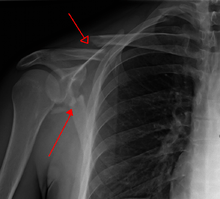

Diagnosis

Most fractures of the scapula can be seen on a chest X-ray; however, they may be missed during examination of the film.[1] Serious associated injuries may distract from the scapular injury,[4] and diagnosis is often delayed.[3] Computed tomography may also be used.[1] Scapular fractures can be detected in the standard chest and shoulder radiographs that are given to patients who have suffered significant physical trauma, but much of the scapula is hidden by the ribs on standard chest X-rays.[4] Therefore, if scapular injury is suspected, more specific images of the scapular area can be taken.[4]